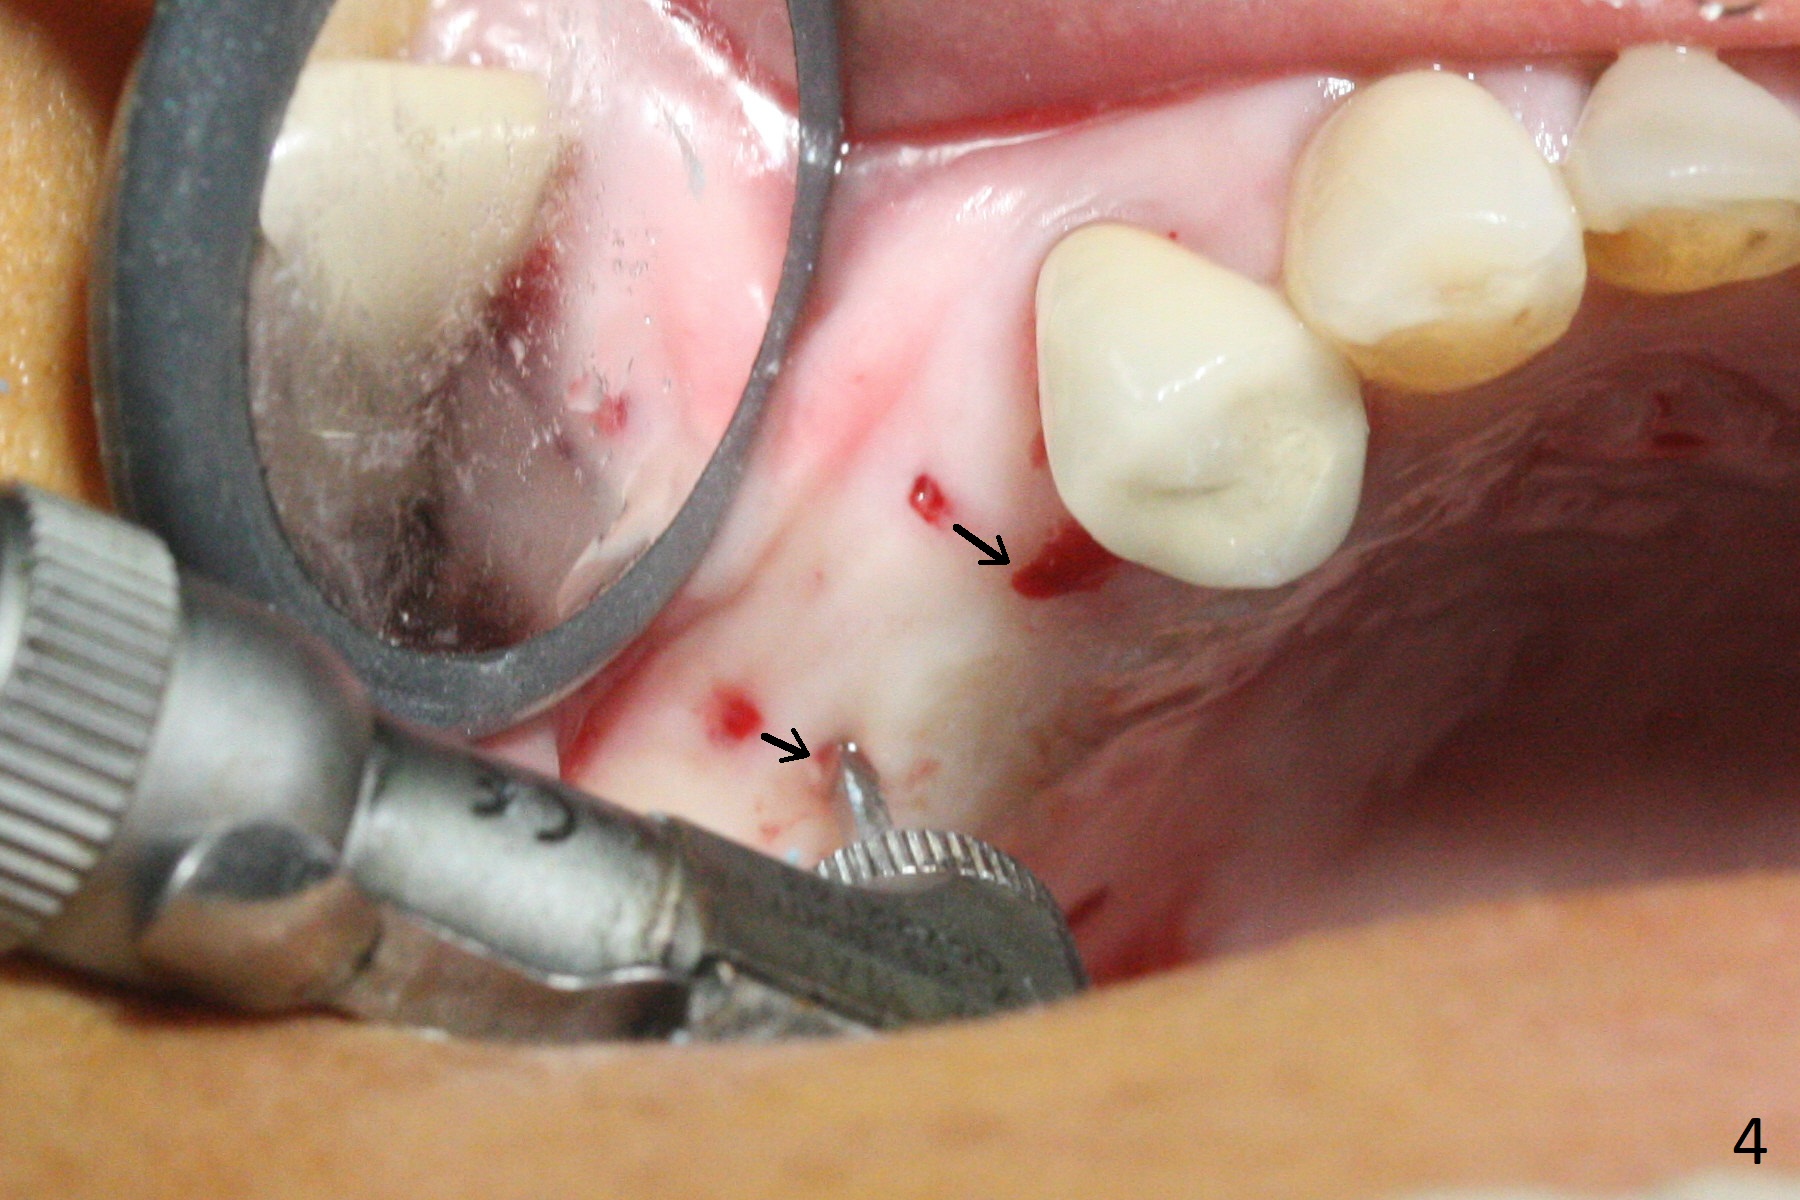

The ridge at #3,4 is wide (Fig.1). A surgical stent is placed (Fig.2) for initial osteotomy (Fig.3). When the stent is removed, the osteotomies need to move palatal (Fig.4 arrows). As two of 1.2 mm drills are in place (Fig.5), mesiodistal trajectories are found off (Fig.6). After the trajectories are corrected (Fig.7), the depth cannot be determined with PA (Fig.8, as compared to Pan (Fig.9)). Following 4.3 and 3.2 mm final drills at #3 and 4, 4.5x13 and 3.8x15 mm implants are placed with insertion torque of 35 and 50 Ncm, followed by 5.5x4(3) and 4.5x4(2) mm abutments (Fig.10). BWs show incomplete placement of the implant at #4 distal (Fig.11,12). Later the implant is placed ~ .5 mm deeper. Periodontal dressing is applied postop. CT-assisted surgical guide must be more efficient for this case with wide ridge. There is no bone loss around the implants 3 moths postop